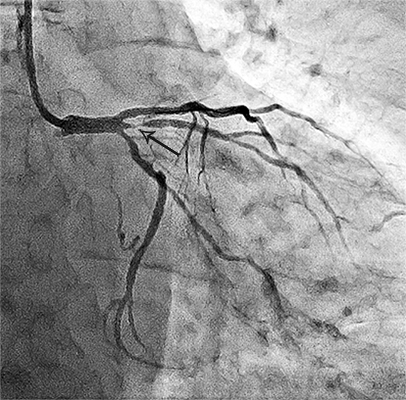

Ангіограми стентування лівої коронарної артерії:

стеноз лівої коронарної артерії    stent    відновлення отвору коронарної артерії

Критичний стеноз лівої коронарної артерії   Розправлений стент    Просвіт артерії відновлено